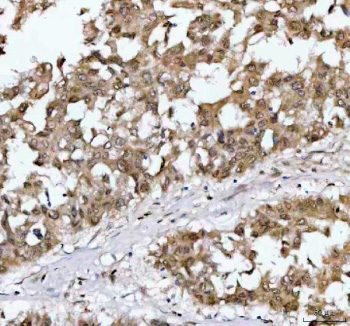

Immunohistochemical staining of NR1D2 using anti-NR1D2 antibody. NR1D2 was detected in a paraffin-embedded section of human liver cancer tissue. Heat mediated antigen retrieval was performed in EDTA buffer (pH 8.0, epitope retrieval solution). The tissue section was blocked with 10% goat serum. The tissue section was then incubated with 2 ug/ml rabbit anti-NR1D2 antibody overnight at 4oC. Peroxidase Conjugated Goat Anti-rabbit IgG was used as secondary antibody and incubated for 30 minutes at 37oC. The tissue section was developed using an HRP secondary and DAB substrate.